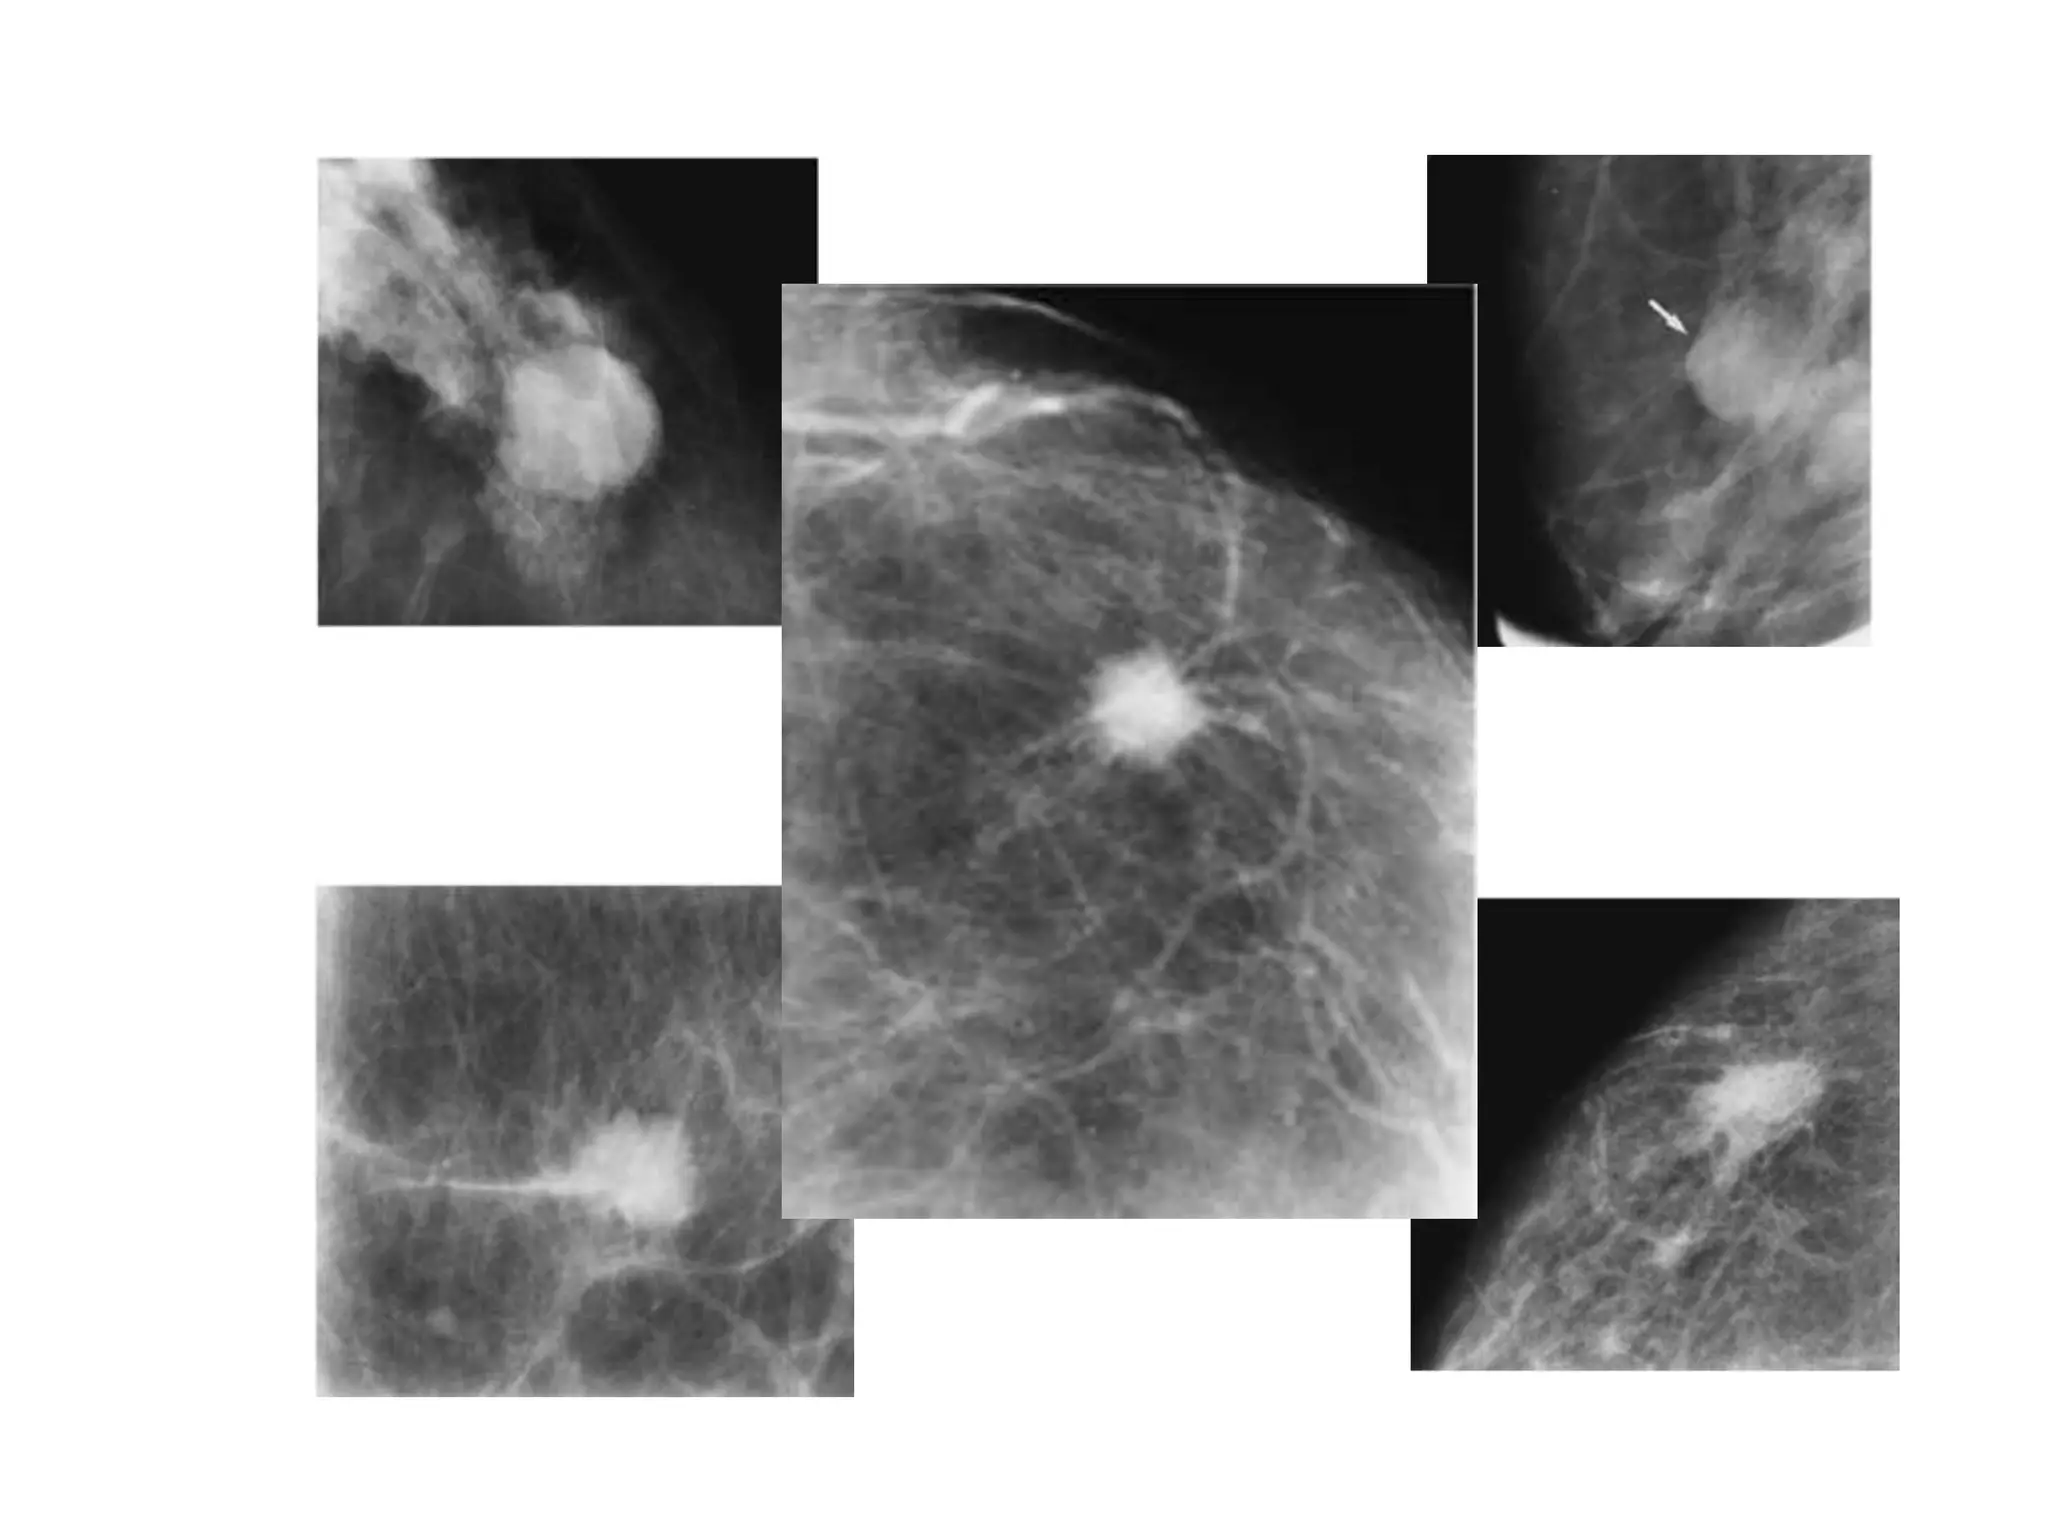

Irregular shaped,

spiculated

margins.

MASS